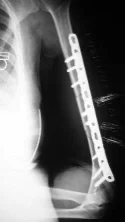

Humeral Shaft Fracture- Management

- Conservative: U-shape slab) / splint / orthosis

- Gravity maintains reduction

Humeral Shaft Fracture

- Management:

- Operative: (plate or IMN)

- Indications:

- Sever displaced Unreduced,

- Bilateral,

- multiple injuries

- floating elbow,

- Needs to use crutches

- Patients’ preference (active, athlete)